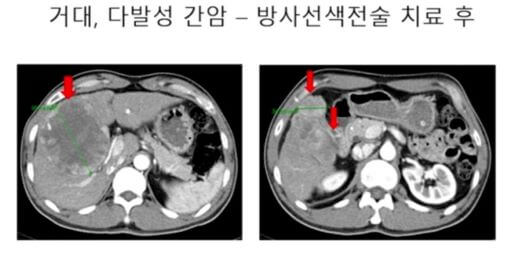

사진에서 화면에 보시는 것처럼, 이분이 거의 그 10년 전에 오신 분인데, 오른쪽 간에 10cm 넘는 큰 간암이 있고 주변에도 위성 결절이라고, 그래서 조그만 간암이 막 오른쪽 간에 많이 퍼져 있는 그런 분이었습니다.

이분은 방사선 색전술이라고 하는 색전술의 하나의 방법 시술로 해서 종양이 매우 많이 줄어들고 괴사가 되고 해서 결국은 오른쪽 간을 절제하는 수술하고, 지금 7년 8년 이상 재발 없이 생존하는 분들도 있다.